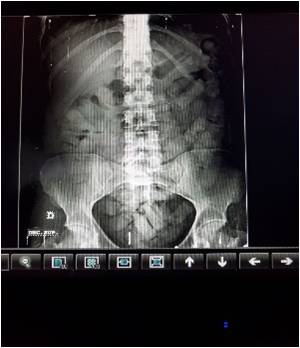

Las dos mujeres manifestaron llevar cocaína en su estómago y partes íntimas al interior de dediles de latex; al ser trasladadas a una unidad médica de Cartagena, expulsaron la sustancia alojada en el estómago durante procedimiento vigilado por personal médico, de igual manera hicieron entrega del más dediles que llevaban al interior de preservativos (condón) en las cavidades genitales.

Al realizar la prueba pericial de campo se estableció al contenido de los dediles se determinó que se trataba de clorhidrato de cocaína, con un peso neto de 2.650 gramos; las capturadas fueron puestas a disposición de la autoridad competente por el delito tráfico, fabricación o porte de estupefacientes.